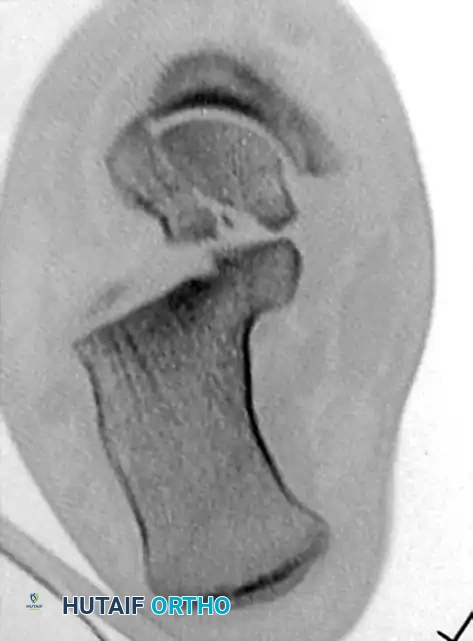

TALAR HEAD FRACTURES: PATHOPHYSIOLOGY AND DIAGNOSIS

Fractures of the head of the talus are relatively uncommon, constituting 5% to 10% of all talar injuries. The talar head articulates with the navicular anteriorly, forming the talonavicular joint—a critical component of the triple joint complex (coxa pedis) responsible for hindfoot inversion and eversion.

Clinical Evaluation and Imaging

Because recognition of this fracture can be difficult, a high index of suspicion must be maintained for any patient presenting with posttraumatic tenderness in the anterior ankle or dorsal midfoot region.

• Physical Examination: Patients typically present with swelling, ecchymosis, and inability to bear weight. Palpation over the talonavicular joint elicits severe pain. The clinician must assess for clinical instability of the triple joint complex, as loss of support at the talonavicular joint compromises the entire medial column.

• Associated Injuries: Injuries to the calcaneocuboid and subtalar joints are highly common and must be actively ruled out.

• Radiographic Evaluation: Plain radiographs (AP, lateral, and oblique views of the foot and ankle) may define the fracture clearly. However, overlapping osseous structures often obscure the true extent of the injury.

• Advanced Imaging: Computed Tomography (CT) is considered mandatory for definitive diagnosis, evaluation of displacement, assessment of intra-articular comminution, and preoperative planning.

Image